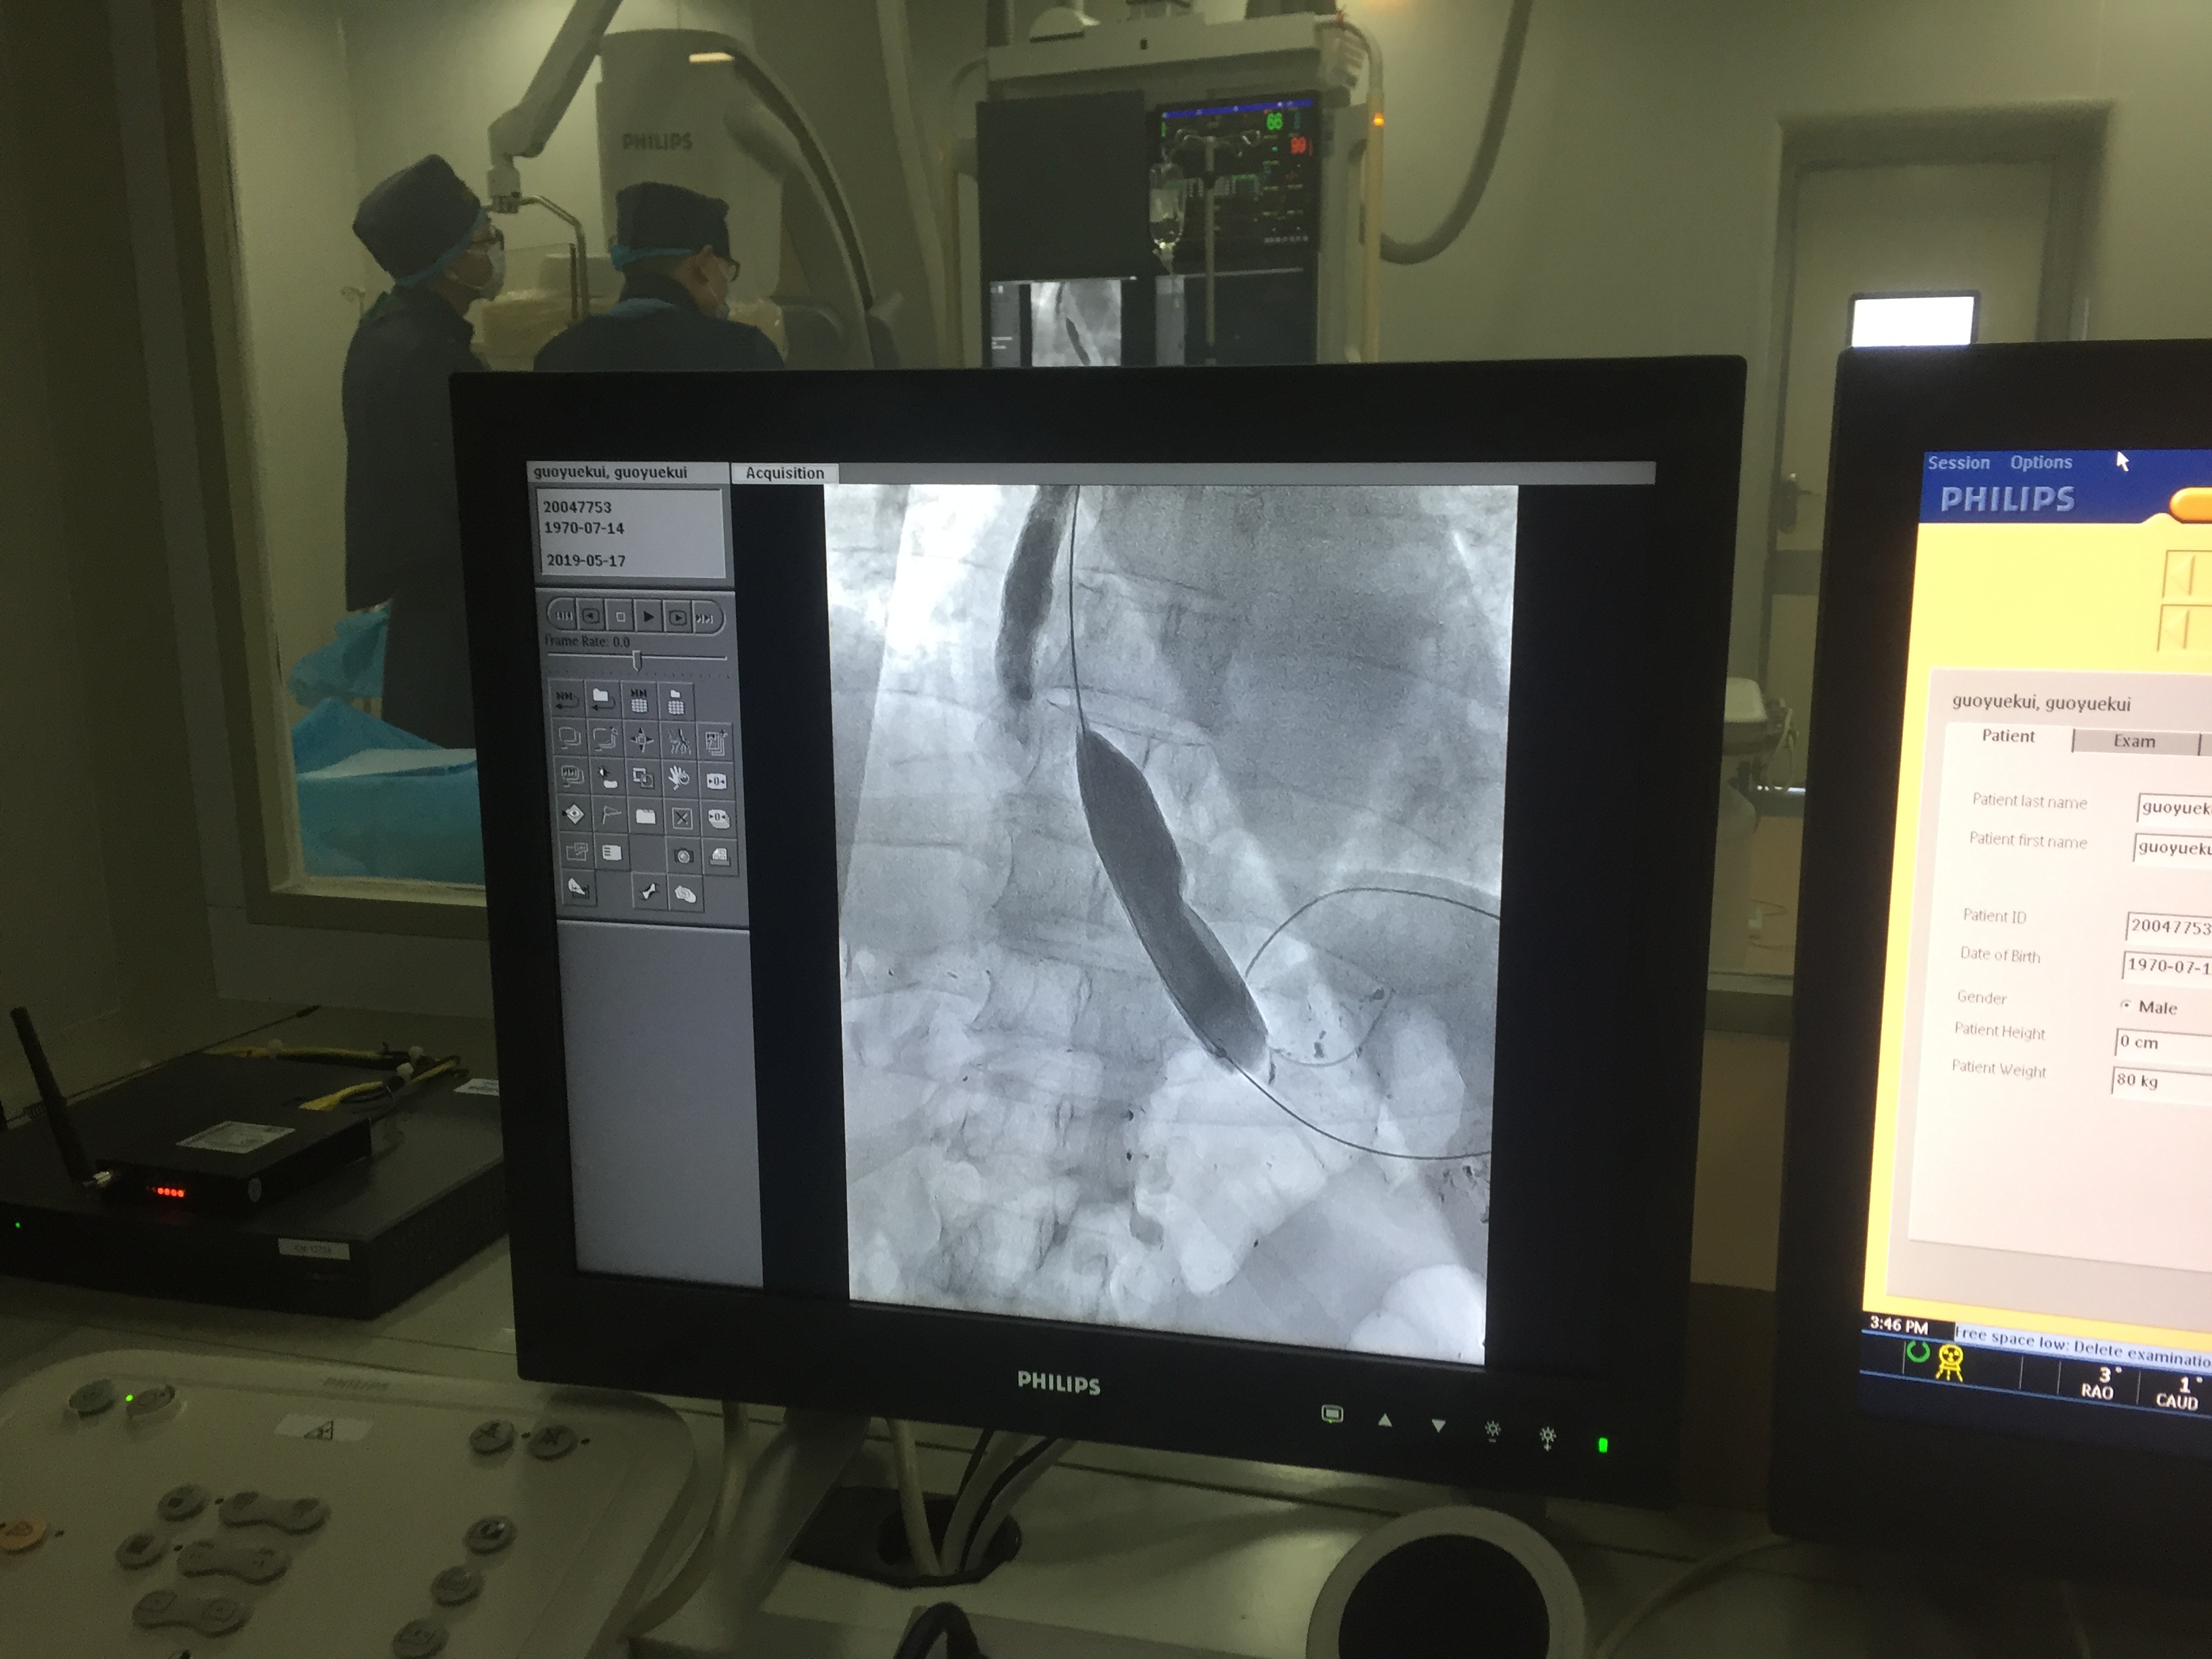

(球囊扩张)

虽然这位患者之前做过球囊扩张又复发了,但是我们还是建议继续做球囊扩张。因为球囊扩张后出现并发症的机会比较小,是均匀的把贲门的肌肉撕开。消化科呢是做Poem手术把括约肌离断,虽然治疗效果也很好,但是有些人会出现严重的反流。过去只是吃东西噎,吃饭的时候出现症状而影响患者生活。但是反流的话24小时都在反流,甚至对人的影响远远超过吞咽困难的影响,而且切开了以后不能再逆转了,而贲门扩张出现复发了,可以再做第二次、第三次来扩张,只要尽量保留你正常的解剖结构,就有机会治愈。如果切断了的话就没有机会了。

(球囊扩张术进行中)